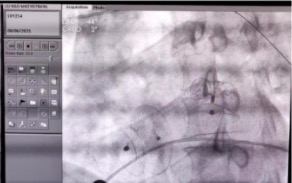

牵拉测试左心耳封堵器稳定性

左心耳封堵器+房间隔缺损封堵器